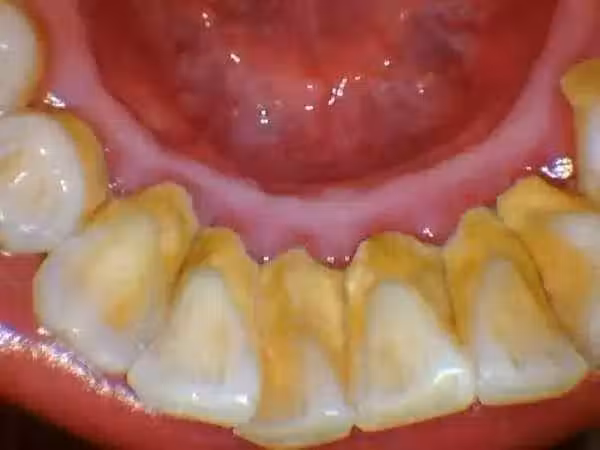

牙結石凡是存在於唾液腺啟齒處的牙齒外表(比方:下顎前牙的舌側外表,上顎後牙的頰側外表)和牙齒的頸部,還有口腔粘膜活動不到的牙齒外表等處。牙結石開始時是軟軟的,會因逐步的鈣化而變硬。它是由75%的磷酸鈣,15-25%的水、有機物、磷酸錳、礦酸鈣及微量的鉀、鈉、鐵所組成。並呈現出黃色、棕色、或許玄色。